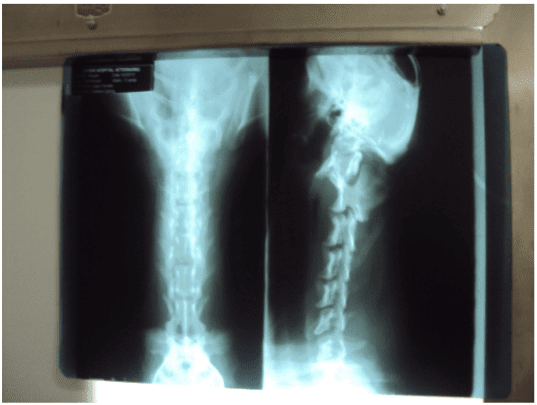

Canino, macho, raça Teckel, com 12 anos. Em 15/02/2011 foi atendido, apresentando a perda de propiocepção de membros anteriores e diminuição dos reflexos, não estava caminhando. Foi solicitado radiografia de região cervical. Foram observadas áreas de calcificação e diminuição do espaço intervertebral entre C2C3, e C5 e C6. Animal foi tratado inicialmente com fármacopuntura (vitamina B12), sendo ainda prescrito [1]Prednisona 20 mg SID por dez dias e eletroacupuntura em dias alternados. Dois dias após o cão havia apresentado melhora clinica e voltou a andar. Foi recomendado eletroacupuntura duas vezes por semana, [2]cloridrato de Tramadol e [3]Carprofeno 25 mg BID. No início de março o animal parou de andar novamente, apresentava sensibilidade na coluna cervical e emagrecimento, o proprietário pediu a Eutanásia. Durante a reavaliação o animal apresentou dor nos membros e diminuições dos reflexos nos membros anteriores. Foi internado para retomar o tratamento com acupuntura, analgésico e antiinflamatório. Após 15 dias de tratamento o animal estava pior. Ficava deitado e não levantava a cabeça e o tronco, iniciou anorexia. Dois dias após, foi suspenso todo o tratamento que estava sendo feito. Iniciou-se o tratamento com o uso do medicamento homeopático [4]Homeopet Pró-coluna® (Calcium fluoricum 10-30, Solanum malacoxylon 10-10,Causticum 10-24, Hypericum perforatum 10-60, Hekla lava 10-24, Apis mellifica 10-24, Plumbum metallicum 10-60, Nux vomica 10-14) 2 borrifadas 3 vezes ao dia.

Radiografias de região cervical. É possível se observar áreas de calcificação e diminuição do espaço intervertebral entre C2-C3, e C5 e C6.